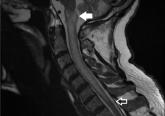

ArticleAcute-onset quadriplegia with hyperreflexiaAuthor:Wael Ghali, MDPublish date: January 3, 2019MRI showed diffuse T2 hyperintensity beginning at the level of the medulla and extending to the level of C7.Read More